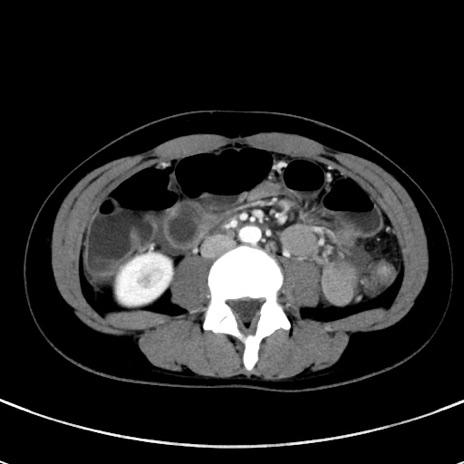

症例17(横断像)

【症例】20歳代女性

【主訴】嘔吐、下腹部痛

【現病歴】昨日夕食後に嘔吐し下腹部痛が出現。本日になっても嘔吐持続し改善しないため来院。

【身体所見】意識清明、BT 37.2℃、BP 108/67mmHg、腹部:平坦、やや硬、下腹部正中から右にかけて圧痛あり、反跳痛軽度あり、tapping pain(+)。

【データ】WBC 13600、CRP 14.94